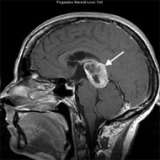

An MRI scan shows a large tumor (arrow) in the pineal region of the brain. The biopsy confirmed glioblastoma, which is rare in this part of the brain. This illustrates the importance of obtaining a tissue biopsy in most cases.

- A magnetic resonance imaging (MRI) of the brain is the most important imaging study. It will show the location, size, and shape of the tumor.